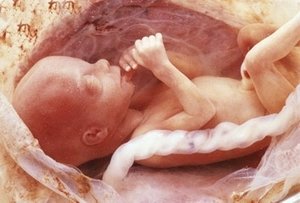

32 неделя беременности узи

РАЗВИТИЕ И ПОЛОЖЕНИЕ РЕБЕНКА В ЖИВОТЕ НА 32 НЕДЕЛЕ БЕРЕМЕННОСТИ

Мозг малыша значительно увеличивается. На 32-ой неделе беременности его объем составляет 75% от мозга взрослого человека. Поэтому увеличивается и головка ребенка, пройдет совсем немного времени, и малыш займет правильное положение перед родами – головкой вниз, спинкой влево.

На 32 неделе беременности ребенок видит. Если на него падает свет, его зрачки сужаются.

Малыш готовится к жизни вне маминого животика: он активно двигает ручками и ножками, глотает околоплодные воды, проводит дыхательную гимнастику для легких, сосет пальчик.